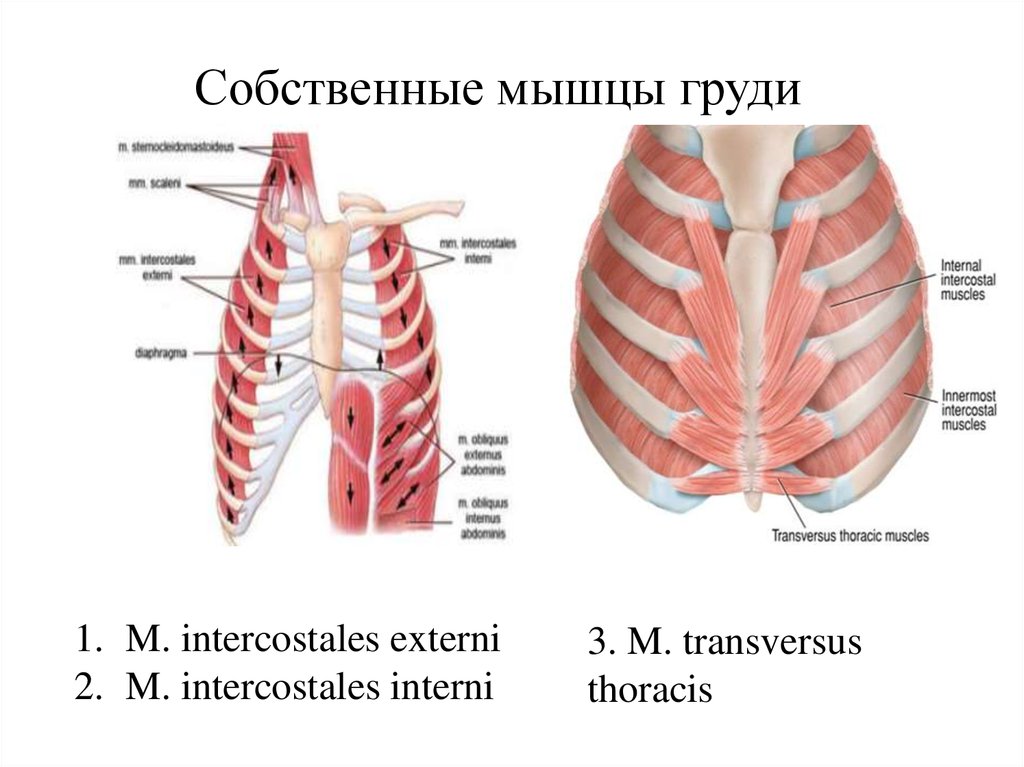

Анатомия межплеврального пространства